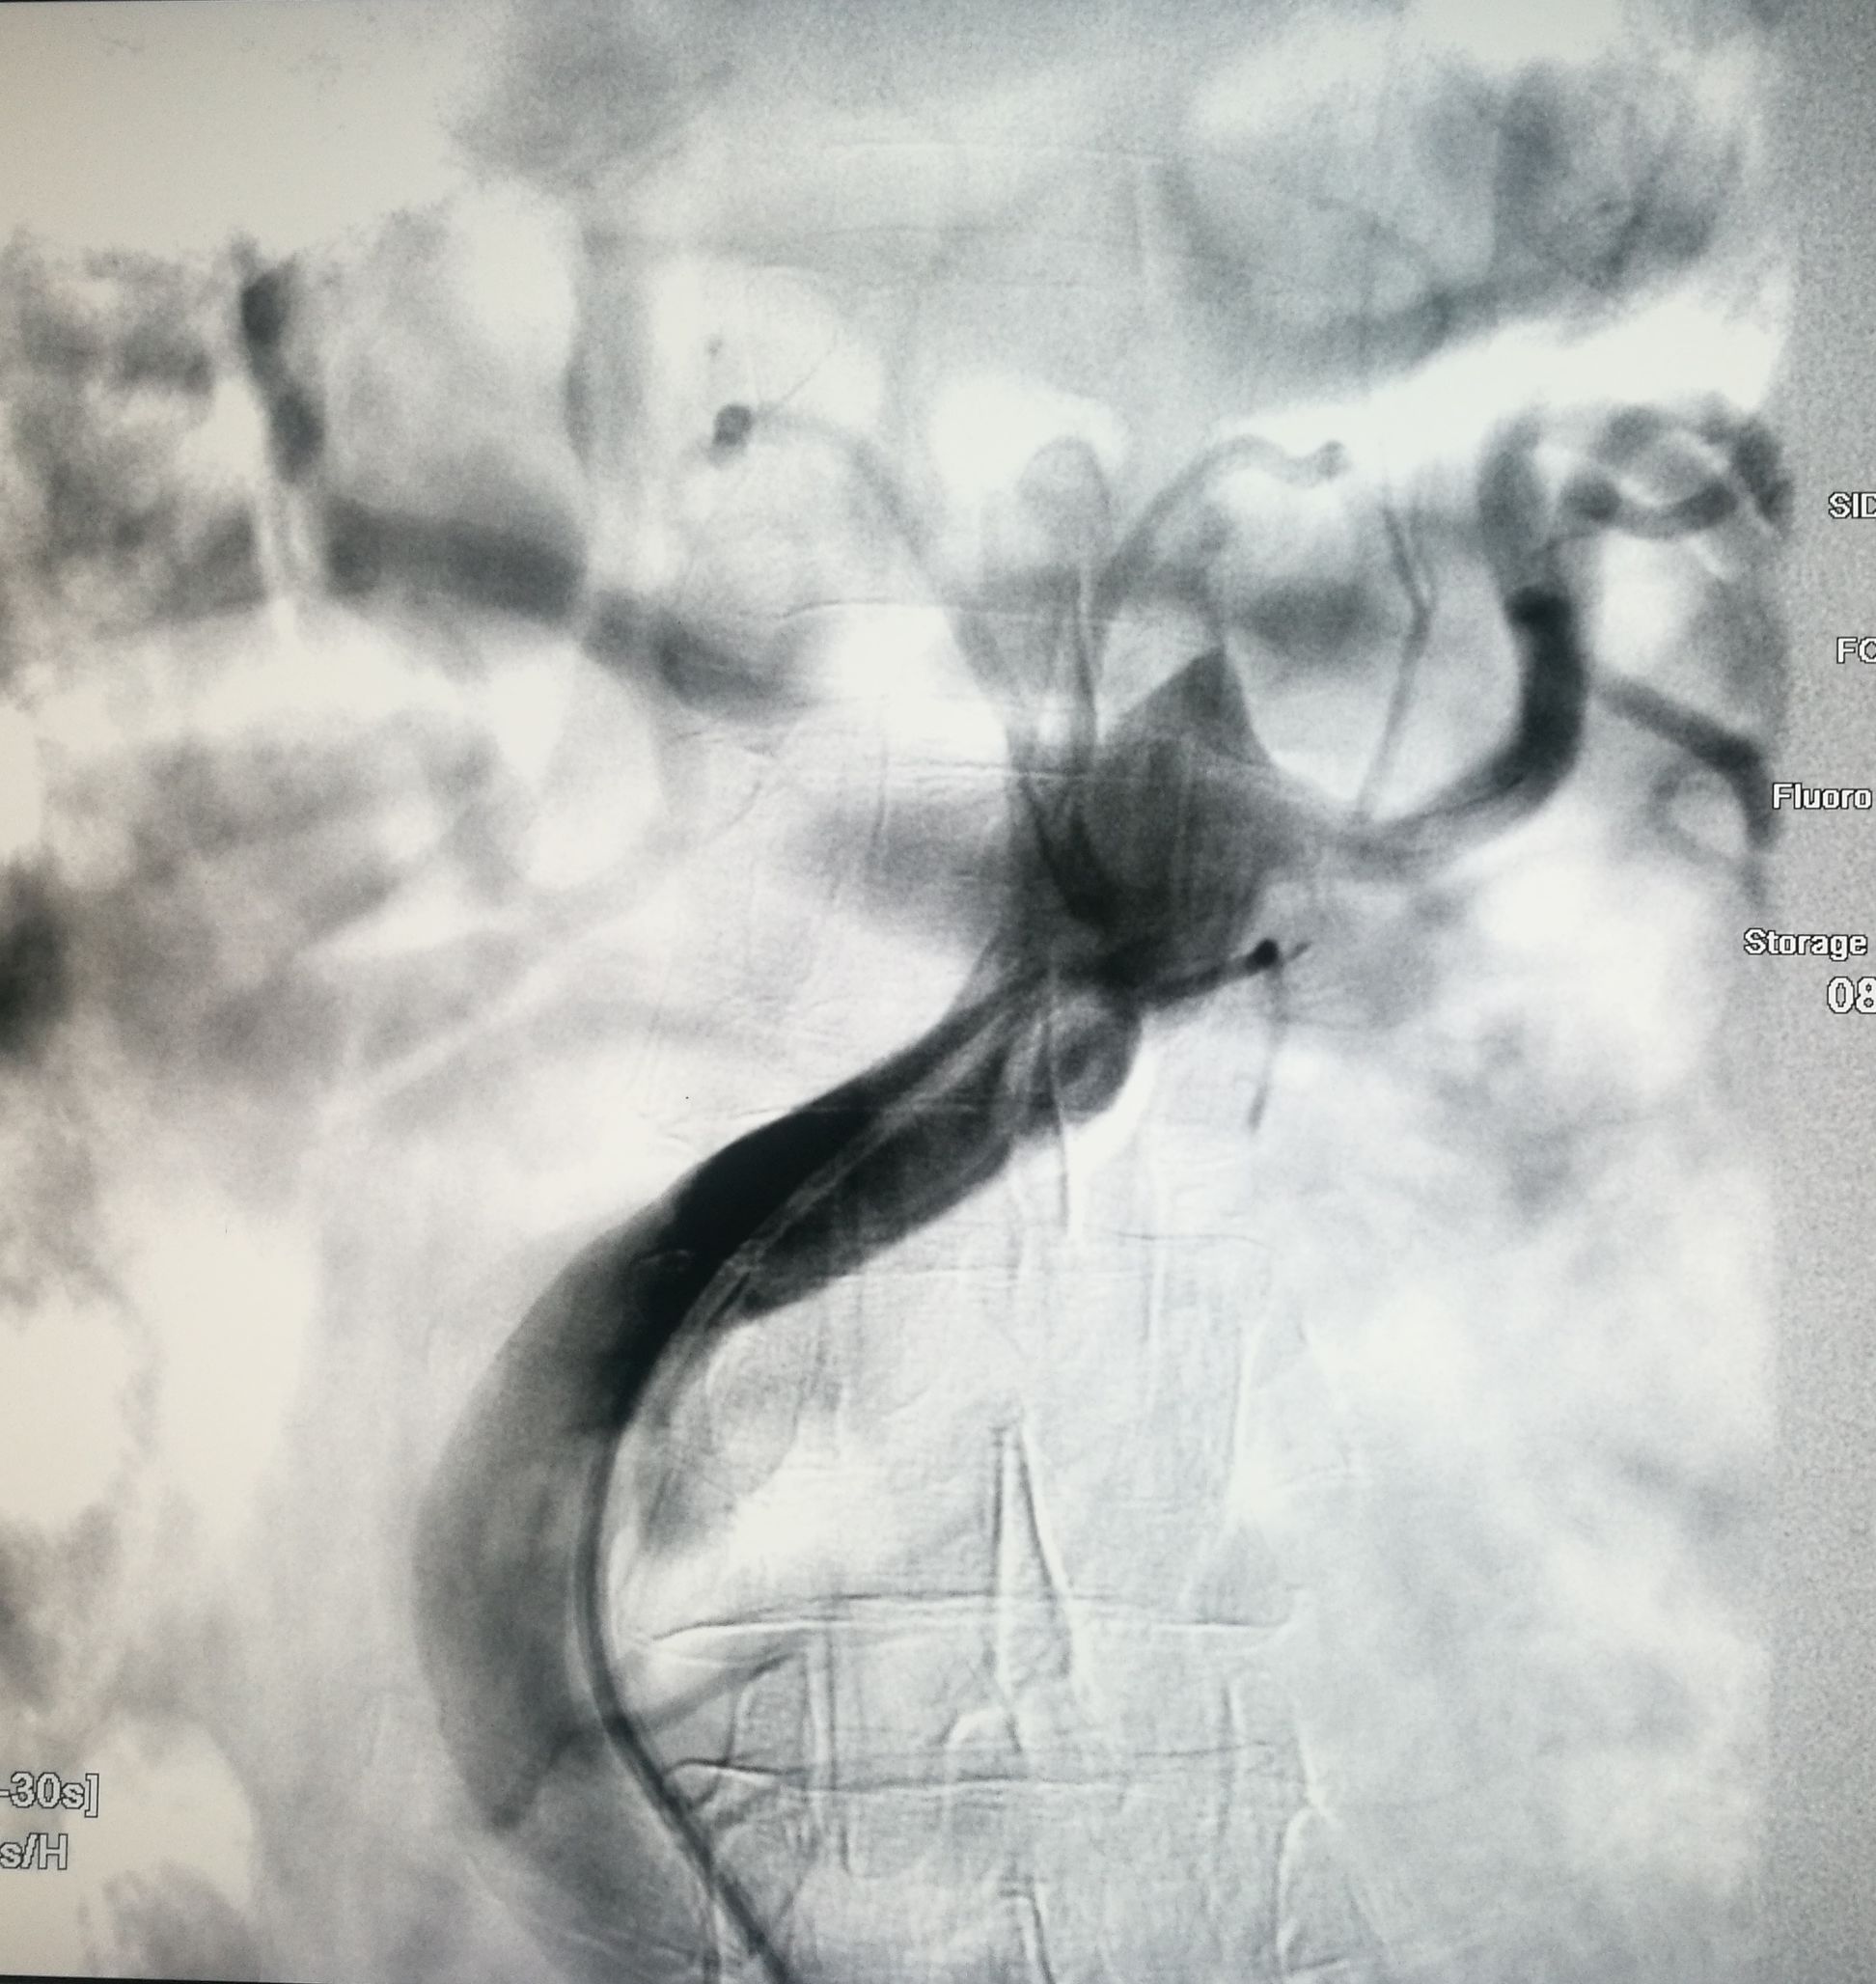

手术在局麻下进行,经右股动脉穿刺置管到升主,经左桡动脉穿刺植入金标猪尾导管,造影,为确认真假腔,加做右前斜位造影,确认股动脉导管在真腔内,测量后植入覆膜支架。由于扭曲严重(腹主,膈肌附近,弓降),支架最初并未贴服大湾侧,支架送过锁骨下动脉后适当回撤,请拉释放导丝,此时支架整体向大弯侧轻微移动,考虑应力已经得到缓解。完全释放支架,定位良好,封堵完全无内漏。

尽管有加硬导丝,但从二维影像上看,支架并未贴着大弯侧走行